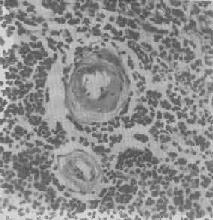

图1-20 脾中央动脉玻璃样变 中央动脉管壁明显增厚,呈玻璃样均质状,管腔变窄 4.粘液性变性 组织间质内出现类粘液的积聚称为粘液样变性(mucoid degeneration)。镜下可见病变处的间质变疏松,充以染成淡蓝色的胶状液体,其中有一些多角形、星芒状细胞散在,并以突起互相联缀。 结缔组织粘液样变性常见于间叶性肿瘤、急性风湿病时的心血管壁、动脉粥样硬化的血管壁。甲状腺功能低下时,全身皮肤的真皮及皮下组织的基质中有较多类粘液(mucoid)及水分潴留,形成粘液水肿(myxedema),其机制可能是甲状腺功能低下时,能促进透明质酸酶活性的甲状腺素分泌减少,致透明质酸(类粘液的主要成分之一)降解减弱而大量潴积于组织内。 粘液样变性当病因消除后可以逐渐消退,但如长期存在,则可引起纤维组织增生,从而导致组织硬化。 5.淀粉样变性 组织内有淀粉样物质沉积称为淀粉样变性(amyloid degeneration,amyloidosis)。淀粉样物质为一种结合粘多糖的蛋白质,遇碘时被染成赤褐色,再加以硫酸则呈蓝色,与淀粉遇碘时的反应相似,故称之为淀粉样物质。此物质常浸润于细胞间或沉积于小血管的基底膜下,或沿网状纤维支架分布(图1-22)。淀粉样物质在HE染色切片中为淡红色均质状,电镜下则为纤细的丝状。

图1-21 肾近曲小管上皮细胞玻璃样小滴变 上皮细胞胞浆内出现大小不等的均质圆形小滴